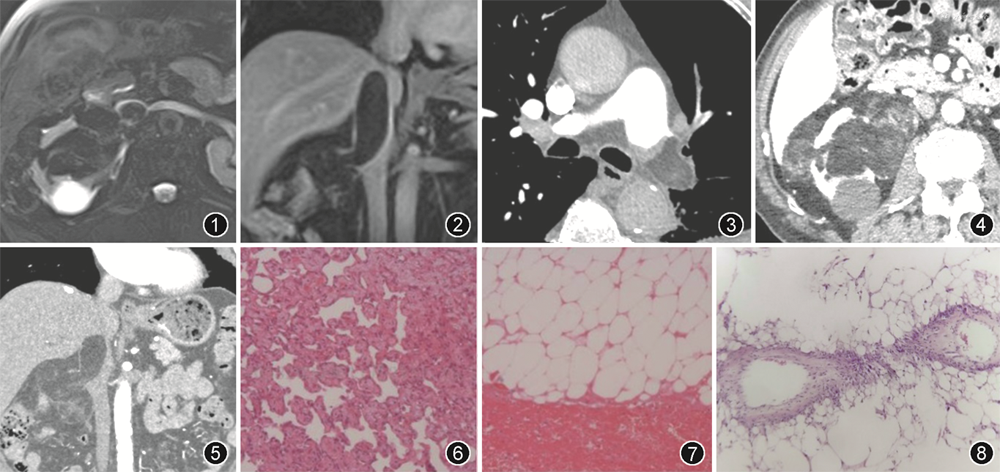

多模态影像学检查:腹部MRI(2020-05-18)示右肾可见不规则脂肪信号为主肿块,右肾静脉与下腔静脉内可见脂肪信号,与右肾肿块直接相连(图1,2)。肺血管CTA(2020-07-16)示左肺动脉干及以远分支管腔内多发中、低密度影,脂肪密度为主,左肺动脉干管腔闭塞(图3)。腹部增强CT(2020-07-20)示右肾巨大肿块,形态不规则,主体位于右肾窦,最大径87 mm×46 mm,其内可见大量脂肪密度及少量絮状中、低密度,肿块直接延伸至右肾静脉、下腔静脉(图4,5)。对比肺动脉栓塞发生前后下腔静脉内瘤栓图像,显示下腔静脉内瘤栓体积在肺动脉栓塞发生后明显减小(图2,5)。PET-CT(2021-07-20)示右肾中下极及肾窦内团块状混杂密度病变,脂肪密度为主,放射性摄取无增高;右肾静脉及下腔静脉内脂肪密度灶,与右肾病变相连,放射性摄取不高;左肺动脉干分叉处及其分支内条状脂肪密度灶,放射性摄取不高。结合临床病史和多模态影像学检查,初步诊断右肾AML,伴右肾静脉、下腔静脉及左肺动脉栓塞。

手术及病理:患者接受肺动脉病损切除术。术中完整剥离主肺动脉内肿块,并剥离左下肺动脉内膜及远端栓子,术后病理为(左肺动脉)脂肪及瘤样组织栓塞,伴血栓形成(图6,7)。患者出院后3个月在当地医院行右肾切除并下腔静脉瘤栓取出术,术中见右肾实质肿物为灰黄色,与肾窦脂肪相连;静脉内瘤栓为脂肪性质,淡黄色,质地松软。显微镜下可见肿块内含有小血管、成熟脂肪组织(图8)和平滑肌组织,术后病理为(右肾)AML。